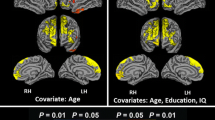

The contrast analysis revealed small foci of 626 voxels specifically associated with the TMTB (Fig. 4; Table 2). The voxels were mainly located in the left dorsomedial frontal region, involving the subgenual and pregenual anterior cingulate gyrus (Brodmann area [BA] 24), the adjacent areas (BA 32 and the superior part of BA 11), the adjacent corpus callosum, and the frontostriatal tract.

Contrast analysis of the TMTB completion time minus the TMTA completion time: VLSM findings and sensitivity analysis of the lesion effect within this contrast map on TMT performance (Z score) showing the disproportionate effect of the lesion on TMTB (left-side structures are shown on the left of the figure). TMT Trail Making Test

The sensitivity analysis (Fig. 4.) showed (1) a significant effect of lesion within this contrast map (p = 0.003) due to an overall slowing in lesioned patients (lesion present: − 1.29 ± 0.16; lesion absent: − 0.81 ± 0.05), (2) a significant effect (p = 0.0001) of the test part, due to a slower time in the TMTB (− 1.39 ± 0.09) than in the TMTA (− 0.704 ± 0.87), and (3) most importantly, a significant lesion × test part interaction (p = 0.0001), related to the expected disproportionate slowing in the TMTB by lesioned patients.

Lastly, the maps for set-shifting did not overlap with those for strategic word search processes (Figs. 4 and 5).